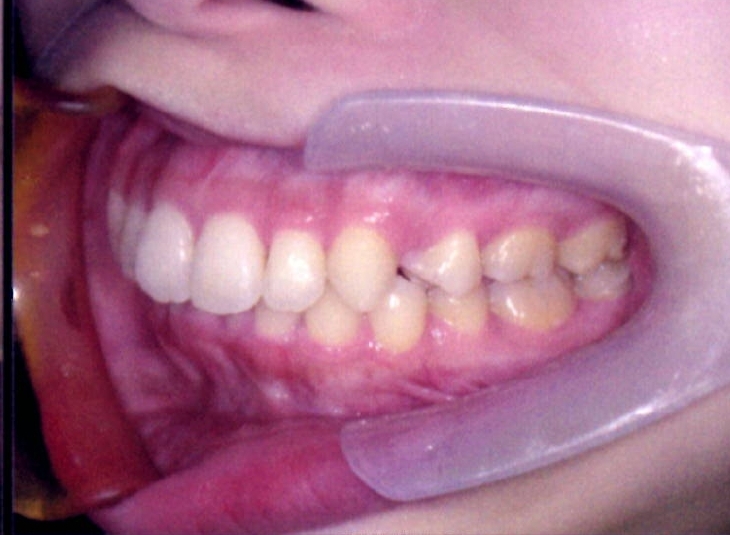

| 主訴・治療前の状態 | 著しい叢生(歯並びのガタガタ)があり、また6歳臼歯(第一大臼歯)が破折していた状態でした。 |

| 治療内容 | 通常の抜歯矯正では第一小臼歯(4番)を抜歯することが多く、その方が治療期間を短縮できますが、小川さんの場合は破折していた6歳臼歯を抜歯し、そのスペースを活用して歯列を整えました。これにより、健康な歯の本数を維持しながら矯正治療を行うことができました。 |

| 治療結果 | 治療前と比較して歯並びが大きく改善し、見た目も大幅に良くなりました。患者様にも大変喜んでいただけた症例です。 |